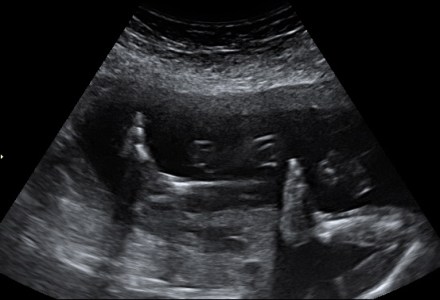

I had my 20 week scan yesterday and these images gave me a sneaky peek into yet, another soul. xx